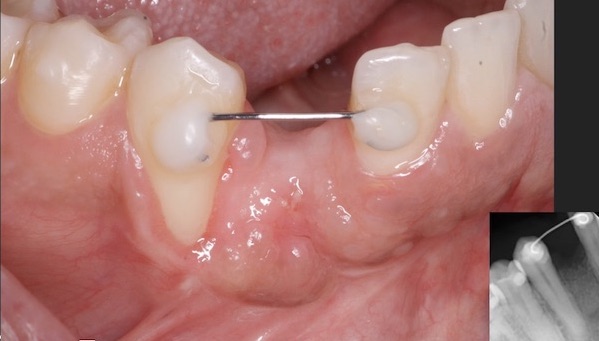

This patient presents with periimplantitis of the lower left quadrant. Removal of existing implants with Guided Bone Regeneration is required. The tent pole technique for GBR was used.